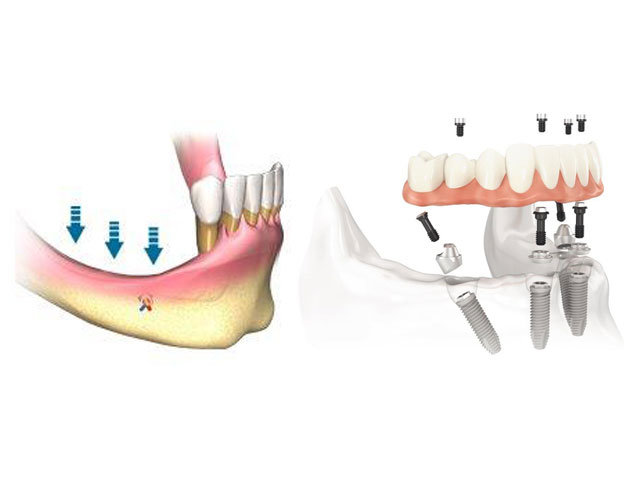

Impianti anche quando c'è poco osso o senza osso

CCon la tecnica computer assistita (All on 4 – All on 6) è possibile inserire, nella maggior parte dei casi, gli impianti a carico immediato anche dove c’è poco osso risparmiando così al paziente complicati e lunghi interventi chirurgici preliminari. NOVITÀ: è possibile avere i denti fissi lo stesso giorno dell’intervento anche in assenza di osso (* implantologia iuxtaossea e implantologia zigomatica). Poche ore per avere denti fissi e masticare immediatamente. Sembra un sogno ma nel nostro studio è realtà.

Implantologia con poco osso

(All on 4 e All on 6)

Grazie all'immagine della Tac tridimensionale (che eseguiamo in studio) e ad un software particolare studiamo il volume dell'osso disponibile e valutiamo l'inserzione degli impianti utilizzando la tecnica dell'All on Four.